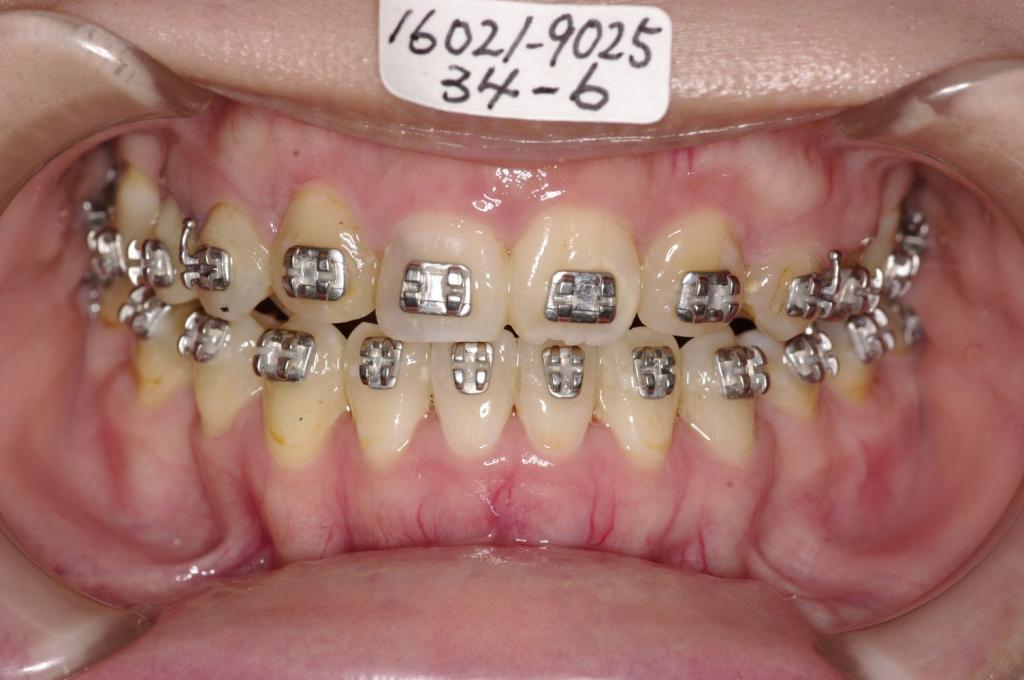

- 顎、顔の歪みの矯正治療

- 歯並びが悪い